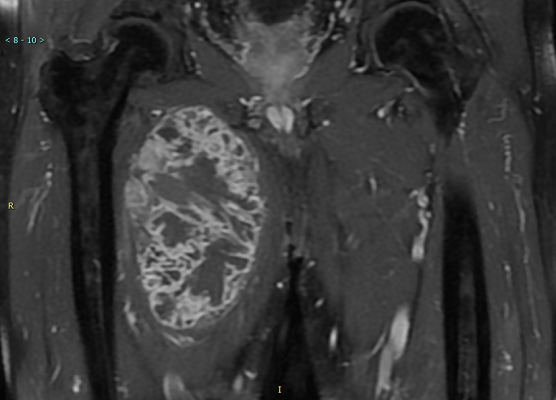

MR所见:右大腿上段长收肌内侧肌间隙内见不规则肿块影,T1WI以等低信号为主,其内见斑片状稍高信号影,增强扫描肿块实性部分及纤维分隔明显强化,呈蜂窝状,邻近肌群受压推挤,局部见脂肪分离征,肿块钻缝生长。

MRI :图像上多表现为分叶状肿块,由于特征性软骨基质的存在,T1WI 呈等或低信号 ( 与肌肉相比) ,肿瘤伴有出血坏死时信号复杂, T2WI 呈混杂高信号,病灶中心的信号强度更高,内可见低信号间隔,把肿瘤分成多个小叶,增强扫描可见间隔强化。

例 1:MRI 平扫 表现为右侧腹股沟区及右大腿上段前方软组织内多发不规则分叶状异常信号影( 图 1a) ,T1WI 低信号, 部分信号不均匀,T2WI 高信号,STIR 呈高信号,其内分隔呈低信号( 图 1b,1c) ,邻近肌群受压、移位, 骨质信号未见异常。

例 2 :X 线摄影表现为右股骨中下段周围见软组织肿块影,内见点状钙化,骨皮质毛糙,可见层状骨膜反应,髓腔内密度不均匀增高 ( 图 2a) 。CT 显示右股骨中下段周围见不规则软组织肿块,包绕右股骨生长,右股骨中下段骨质密度不均匀,见多发筛孔状骨质破坏区( 图 2b) ,增强扫描病灶实性成分不均匀轻度强化,内见多发血管影及斑片状无强化区( 图 2c) 。MRI 表现为不规则软组织肿块包饶右股骨中下段,T1WI 呈等信号,T2WI 及 STIR 呈高信号,内见多发低信号间隔( 图 2e,2f) ,右股骨中下段骨质信号异常,T1WI 低信号,T2WI 及 STIR 高信号。